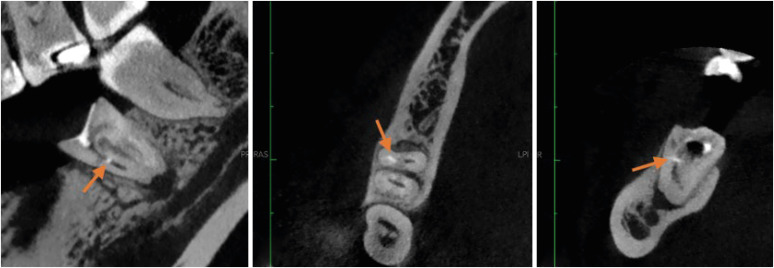

研究目的本研究旨在通过锥形束计算机断层扫描(CBCT)分析,调查牙髓治疗程序错误的频率和类型:样本包括 96 张 CBCT 扫描图,涵盖 122 颗牙根完全成形的恒牙。误差包括穿孔、器械折断、牙槽移位、遗漏牙槽和根尖充填极限不足。此外,还对潜在的风险因素进行了分析和统计建模:结果:最常见的程序错误是根尖充填极限不足,其次是根管运输、穿孔、遗漏根管和器械折断。各种程序错误与特定因素之间存在明显的统计学关联。这些因素包括:根管运输和根管壁,其中颊侧壁最常受到影响;遗漏的根管和牙齿类型,尤其是腭侧和第二中颊面管;根尖充填限值不足和根弯曲度,显示出严重弯曲的根管向中侧方向的偏差更大;根尖充填不足和存在钙化,其中以充填不足最为常见;根管运输和根尖周病变,特别是偏向颊侧方向;以及穿孔方向和根尖周病变,其中以偏向颊侧方向最为常见。结论:CBCT 是识别程序错误和相关因素的重要工具,对预防和管理这些错误至关重要。

Materials and methods: The sample consisted of 96 CBCT scans, encompassing 122 permanent teeth with fully formed roots. Errors included perforation, instrument fracture, canal transportation, missed canals, and inadequate apical limit of filling. Additionally, potential risk factors were analyzed and subjected to statistical modeling.

Results: The most frequent procedural error observed was the inadequate apical limit of filling, followed by canal transportation, perforation, missed canal, and instrument fracture. Statistically significant associations were identified between various procedural errors and specific factors. These include canal transportation and root canal wall, with the buccal wall being the most commonly affected; missed canal and tooth type, particularly the palatine and second mesiobuccal canal canals; inadequate apical limit of filling and root curvature, showing a higher deviation to the mesial direction in severely curved canals; inadequate apical limit of filling and the presence of calcifications, with underfilling being the most frequent; canal transportation and periapical lesion, notably with deviation to the buccal direction; and the direction of perforation and periapical lesion, most frequently occurring to buccal direction.